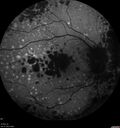

79 year old vision is in for a checkup with no visual complaints in the left eye. This is her better eye. VA 20/200 OD, 20/50 OS. 3 years ago she had a CRVO in the left eye. She is also diabetic for 20 years, has carotid insufficiency and anemia. Left eye shows CME. This was not treated and the vision improved to 20/40 over the next year although mild edema persisted.